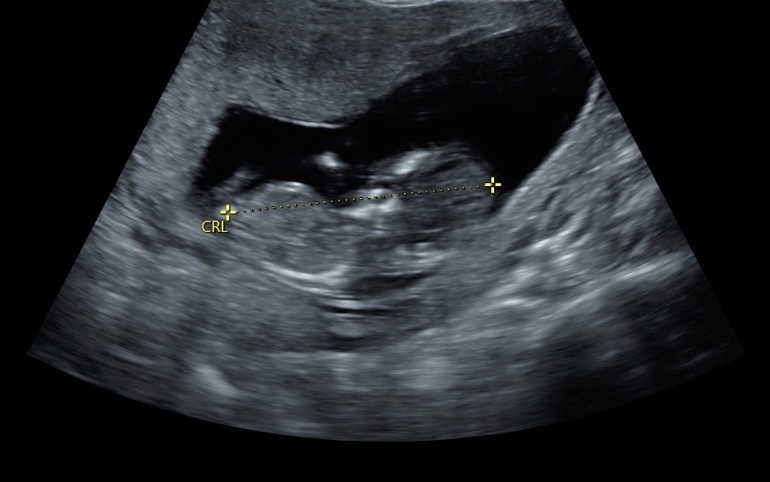

Пол малышаДевочки, давайте погадаем! Последнее УЗИ было на сроке 11,4 недель, но врач не рискнула предположить, сказала рановато! Я не совсем в этом разбираюсь, видно ли тут половой бугорок или нет, может кто-то понимает?

Спасибо))) и доктор так сказала, что вначале типа одинаково у них все, на 13 неделе только формируются органы. Но говорят что по наклону этого бугорка можно определить, но я не понимаю в этом ничего)